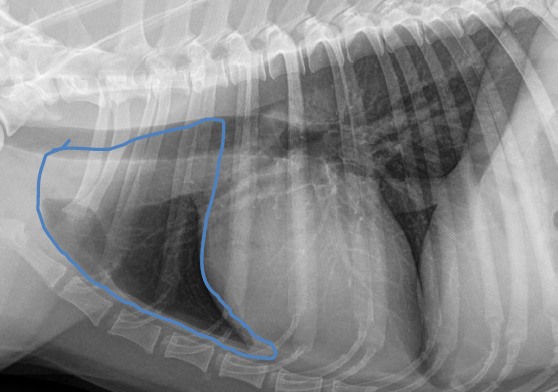

Middle mediastinum

Sternal lymph node

Mediastinal lymph node

Tracheobronchial lymph node

Thymus

Trachea